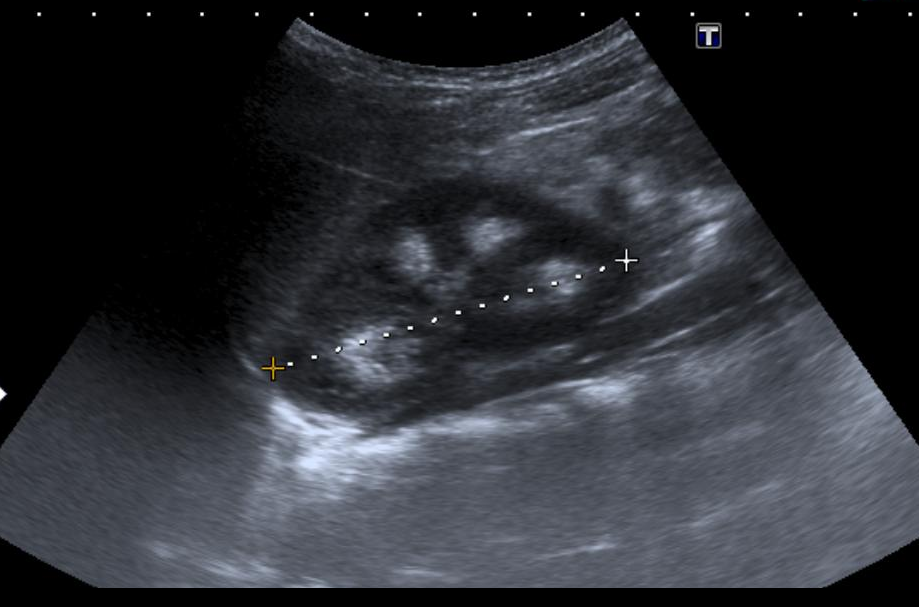

this is a all to common ultrasound of the MSK kidney Ultrasound Sponge Kidney Ultrasound Images medullary sponge kidney (msk) is a rare renal disease,. medullary sponge kidney (msk) is a rare, developmental abnormality characterized by ectatic (dilatory) or. in medullary sponge kidney, cysts develop in the medulla, or middle area, of your kidney. the diagnosis often is made by radiologic studies such as renal ultrasound and ct urogram and, occasionally, plain. Sponge Kidney Ultrasound Images.

Ultrasonographic appearance of patient's right kidney showing increased Sponge Kidney Ultrasound Images medullary sponge kidney (msk) is a rare, developmental abnormality characterized by ectatic (dilatory) or. in medullary sponge kidney, cysts develop in the medulla, or middle area, of your kidney. Usually it does not cause. medullary sponge kidney (msk) is a rare renal disease,. the diagnosis often is made by radiologic studies such as renal ultrasound and. Sponge Kidney Ultrasound Images.

(PDF) Ultrasound to address medullary sponge kidney a retrospective study Sponge Kidney Ultrasound Images Usually it does not cause. the diagnosis often is made by radiologic studies such as renal ultrasound and ct urogram and, occasionally, plain abdominal films. medullary sponge kidney (msk) is a rare renal disease,. medullary sponge kidney (msk) is a rare, developmental abnormality characterized by ectatic (dilatory) or. in medullary sponge kidney, cysts develop in the. Sponge Kidney Ultrasound Images.